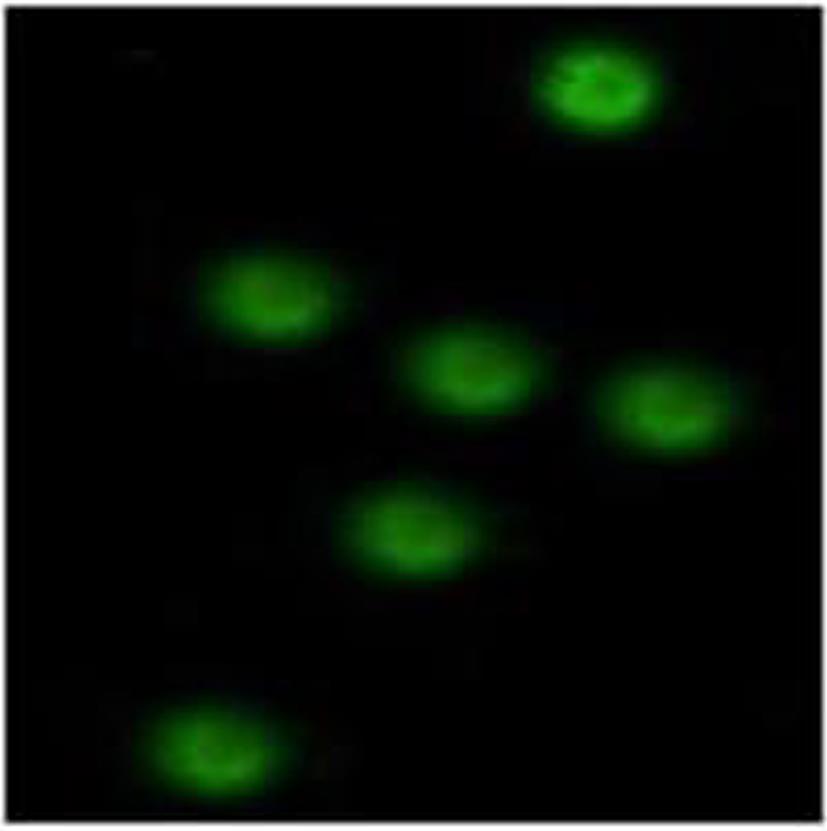

中国旱獭Ⅰ型干扰素受体β亚基克隆、表达及功能初步鉴定

2024, 40(2): 278-283. DOI: 10.12449/JCH240210

摘要(839) HTML (316) PDF (920KB)(56)

摘要:

目的  克隆中国旱獭Ⅰ型干扰素受体β亚基(mhIFNAR2)的基因,并进行抗体制备及功能鉴定。  方法  应用RT-PCR技术,从中国旱獭脾组织中扩增得到序列,克隆至原核表达载体pRSET-B,表达重组蛋白,电泳和Western Blot法鉴定;重组蛋白常规免疫BALB/c小鼠制备其胞外段多克隆抗体,免疫组化、免疫荧光和Western Blot法鉴定;再通过siRNA阻断的方法检测其功能。计量资料多组间比较采用方差分析,进一步两两比较采用LSD-t检验。  结果  从mhIFNAR2扩增出149~1 300 bp片段,其同源性在分析的种属中以土拨鼠最高,可达98.05%。成功地构建了表达胞外段mhIFNAR2(50-181aa)蛋白的原核表达质粒,命名为pRSET-B.mhIFNAR2;其表达重组蛋白分子量27 kD,纯化后纯度约为95%,浓度约为160 μg/mL。用纯化的重组蛋白常规免疫BALB/c小鼠后,获得1∶1 000的特异性多克隆抗体,用免疫组化及免疫荧光可见细胞膜、细胞质有表达。合成的三条siRNA,其中有一条起始于277位点的siRNA(siRNA277)与空白对照及阴性对照相比,可以沉默目的基因的表达,并能减弱干扰素的信号通路(P值均<0.05)。  结论  获得mhIFNAR2的部分序列,成功地制备出抗mhIFNAR2胞外段多克隆抗体,该抗体有较高的效价和特异性,并能用于免疫组化、免疫荧光及Western Blot的检测。用siRNA277可以抑制目的基因的表达,并能阻断干扰素的信号通路。